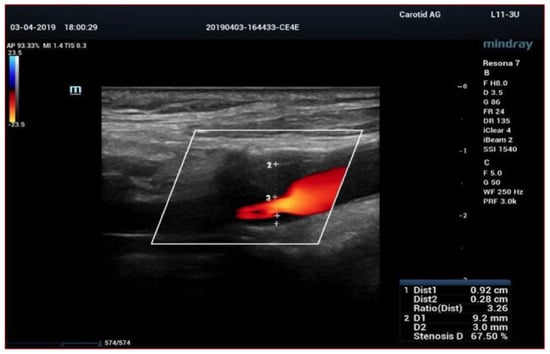

4. Color-Doppler Ultrasound (CDUS)

6. High Frame Rate Vector Flow (V-Flow) and 3D Arterial Analysis Ultrasound (3D-US)

- Fresilli, D.; Di Leo, N.; Martinelli, O.; Di Marzo, L.; Pacini, P.; Dolcetti, V.; Del Gaudio, G.; Canni, F.; Ricci, L.I.; De Vito, C.; et al. 3D-Arterial analysis software and CEUS in the assessment of severity and vulnerability of carotid atherosclerotic plaque: A comparison with CTA and histopathology. Radiol. Med. 2022, 127, 1254–1269. [Google Scholar] [CrossRef] [PubMed]